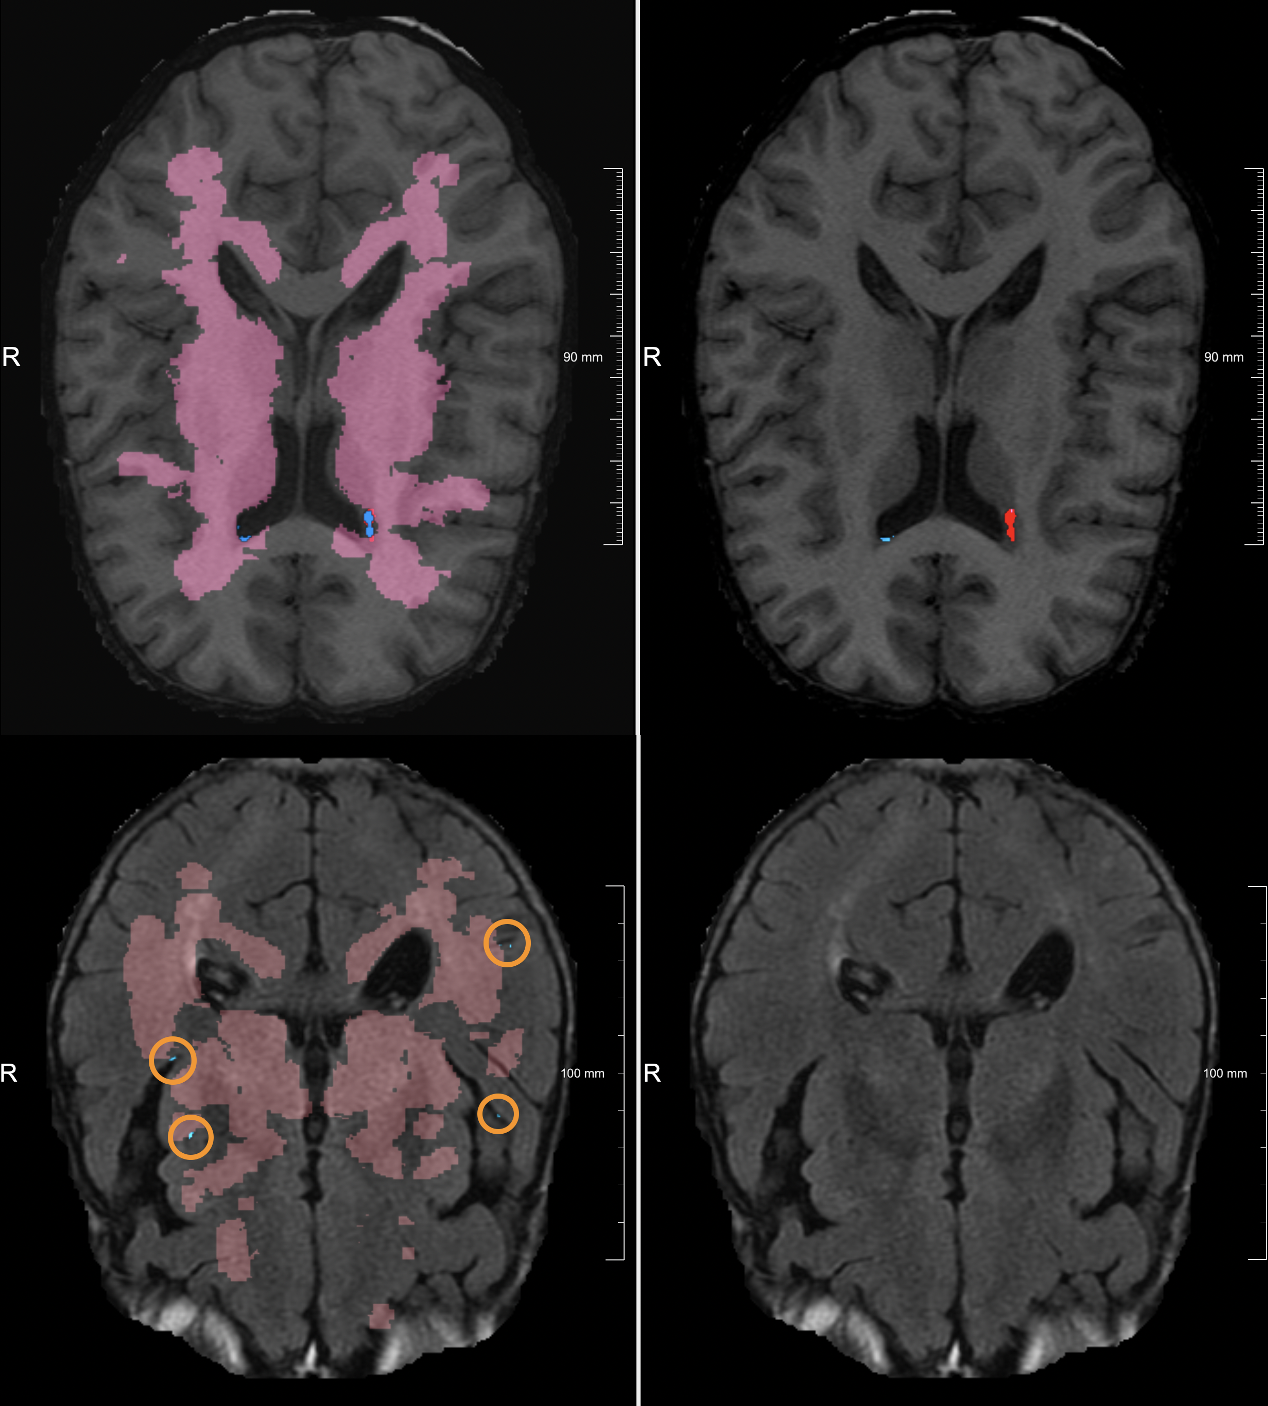

From the SMART-MR study [Biesbroek2013], we included 98 subjects for which manual segmentation of lacunes were available; and combined this with the 40 training subjects of the VALDO challenge. All images were registered to the MNI-152 [Fonov2011] atlas to create a lacune prevalence map. The resulting map (Figure 1) was made symmetric by mirroring, dilated by 7 mm in all directions, and the ventricles and CSF were removed.

Figure 1: The final lacune prevalence map in MNI152-space is shown on the left. Ventricles and extracerebral CSF were removed from the map with a CSF mask (light-blue on the right).

Visual inspection of the results showed that most of the lacunes were correctly detected. An example is shown in Figure 4. However, the predicted binary mask does not precisely match with the ground truth. In some cases, the prediction was a bit smaller compared to its ground truth. A small number of false positive detections remain.

Figure 5 shows the positive and negative effects of the lacune prevalence mask. Most of the times, the lesion prevalence map correctly removes false positive detections; as can be seen in the bottom row of Figure 5. Unfortunately, sometimes the lesion prevalence map also removes a true positive; as can be seen in the top row of Figure 5. This is most likely caused by an image registration error, where the close proximity of the lacune to the ventricles caused a misalignment.

Figure 5: The first pair of images (top row) shows a correctly segmented lacune which was later removed by the prevalence map. The second pair (bottom row) shows how false positives are removed by the prevalence map.